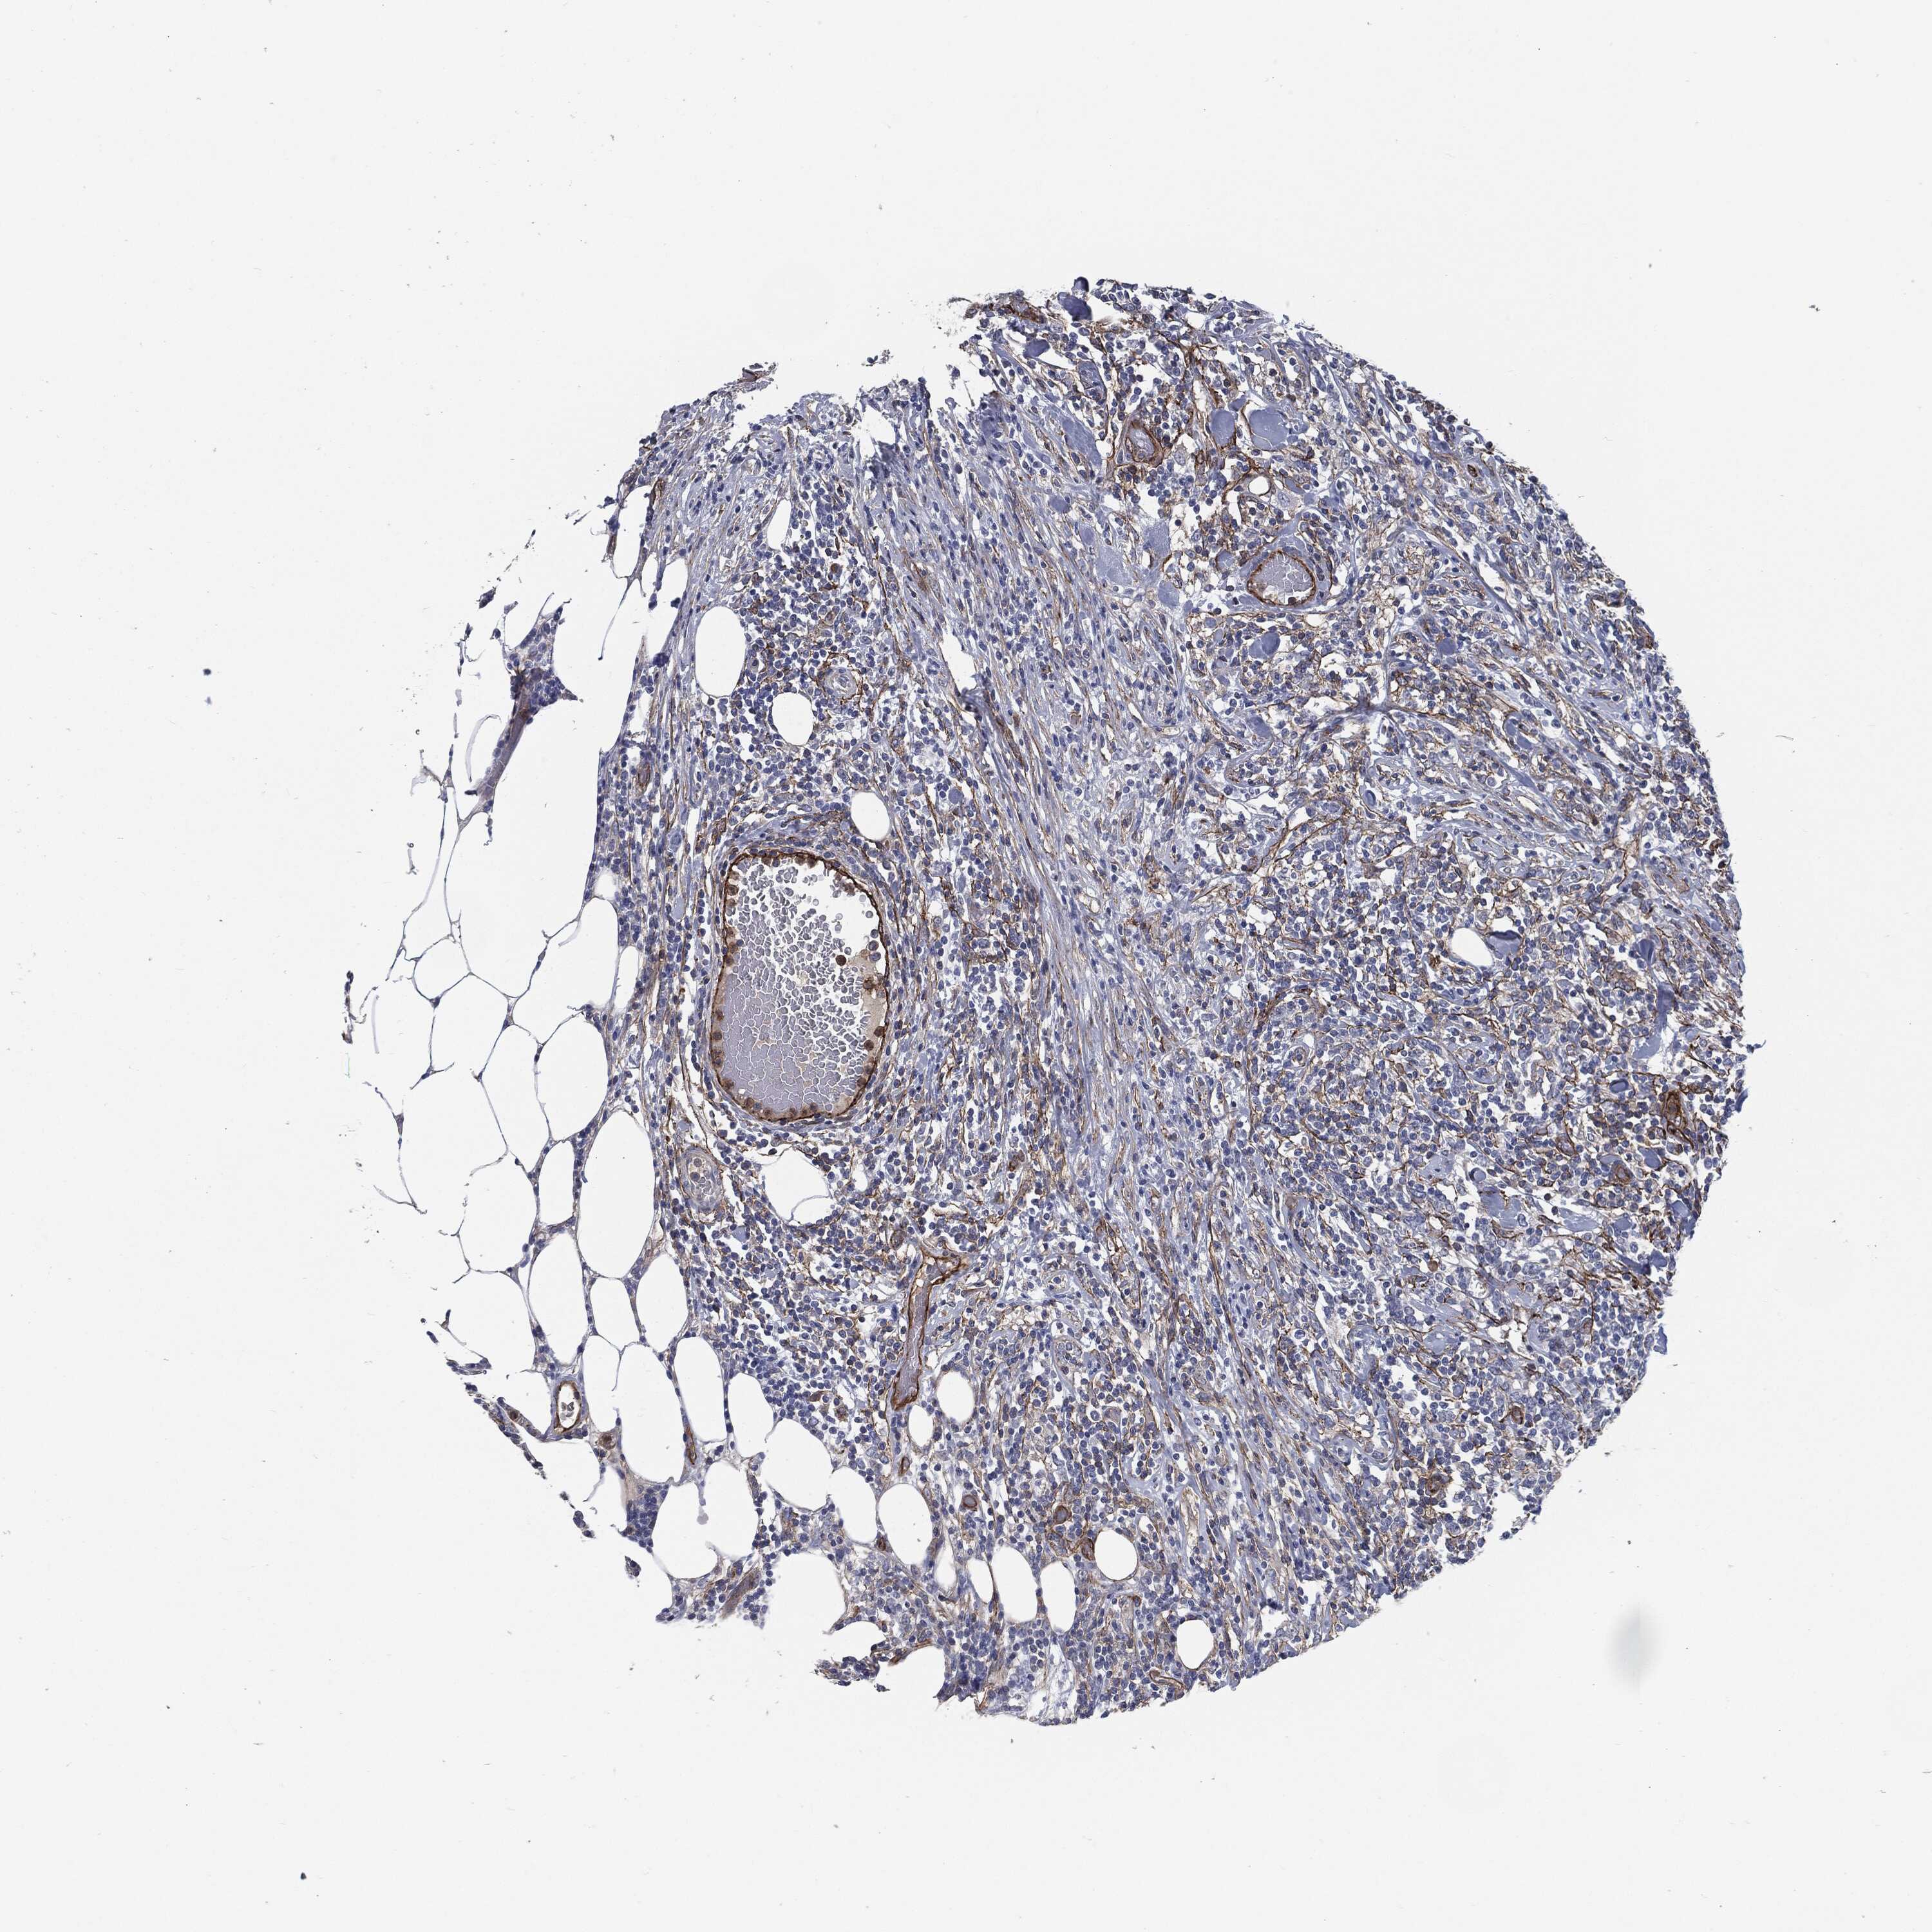

CANCER LYMPHOMA Show tissue menu

LYMPHOMA - Protein expressioni

A mouse-over function shows sample information and annotation data. Click on an image to view it in a full screen mode. Samples can be filtered based on level of antibody staining by selecting one or several of the following categories: high, medium, low and not detected. The assay and annotation is described here.

Each image is clickable and will lead to virtual microscopy that enables deeper exploration of all samples and also displays staining intensity scores, fraction scores and subcellular localization as well as patient and tissue information for each sample.

Antibody HPA020095

Antibody HPA020138

Antibody CAB010878

Antibody CAB080402

Hodgkin's disease, NOS

Malignant lymphoma, non-Hodgkin's type, High grade

Malignant lymphoma, non-Hodgkin's type, Low grade